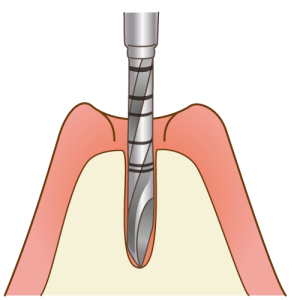

コンテンツをスキップ「第二の永久歯」をつくるための治療インプラント治療とは、歯を失ってしまった部分を補うための治療法です。

「インプラント」と呼ばれる人工歯根を歯を失ってしまった部分に埋め込み、その上に人工歯を装着することで、まるで自分の歯のような見た目や噛み心地を回復させることができます。